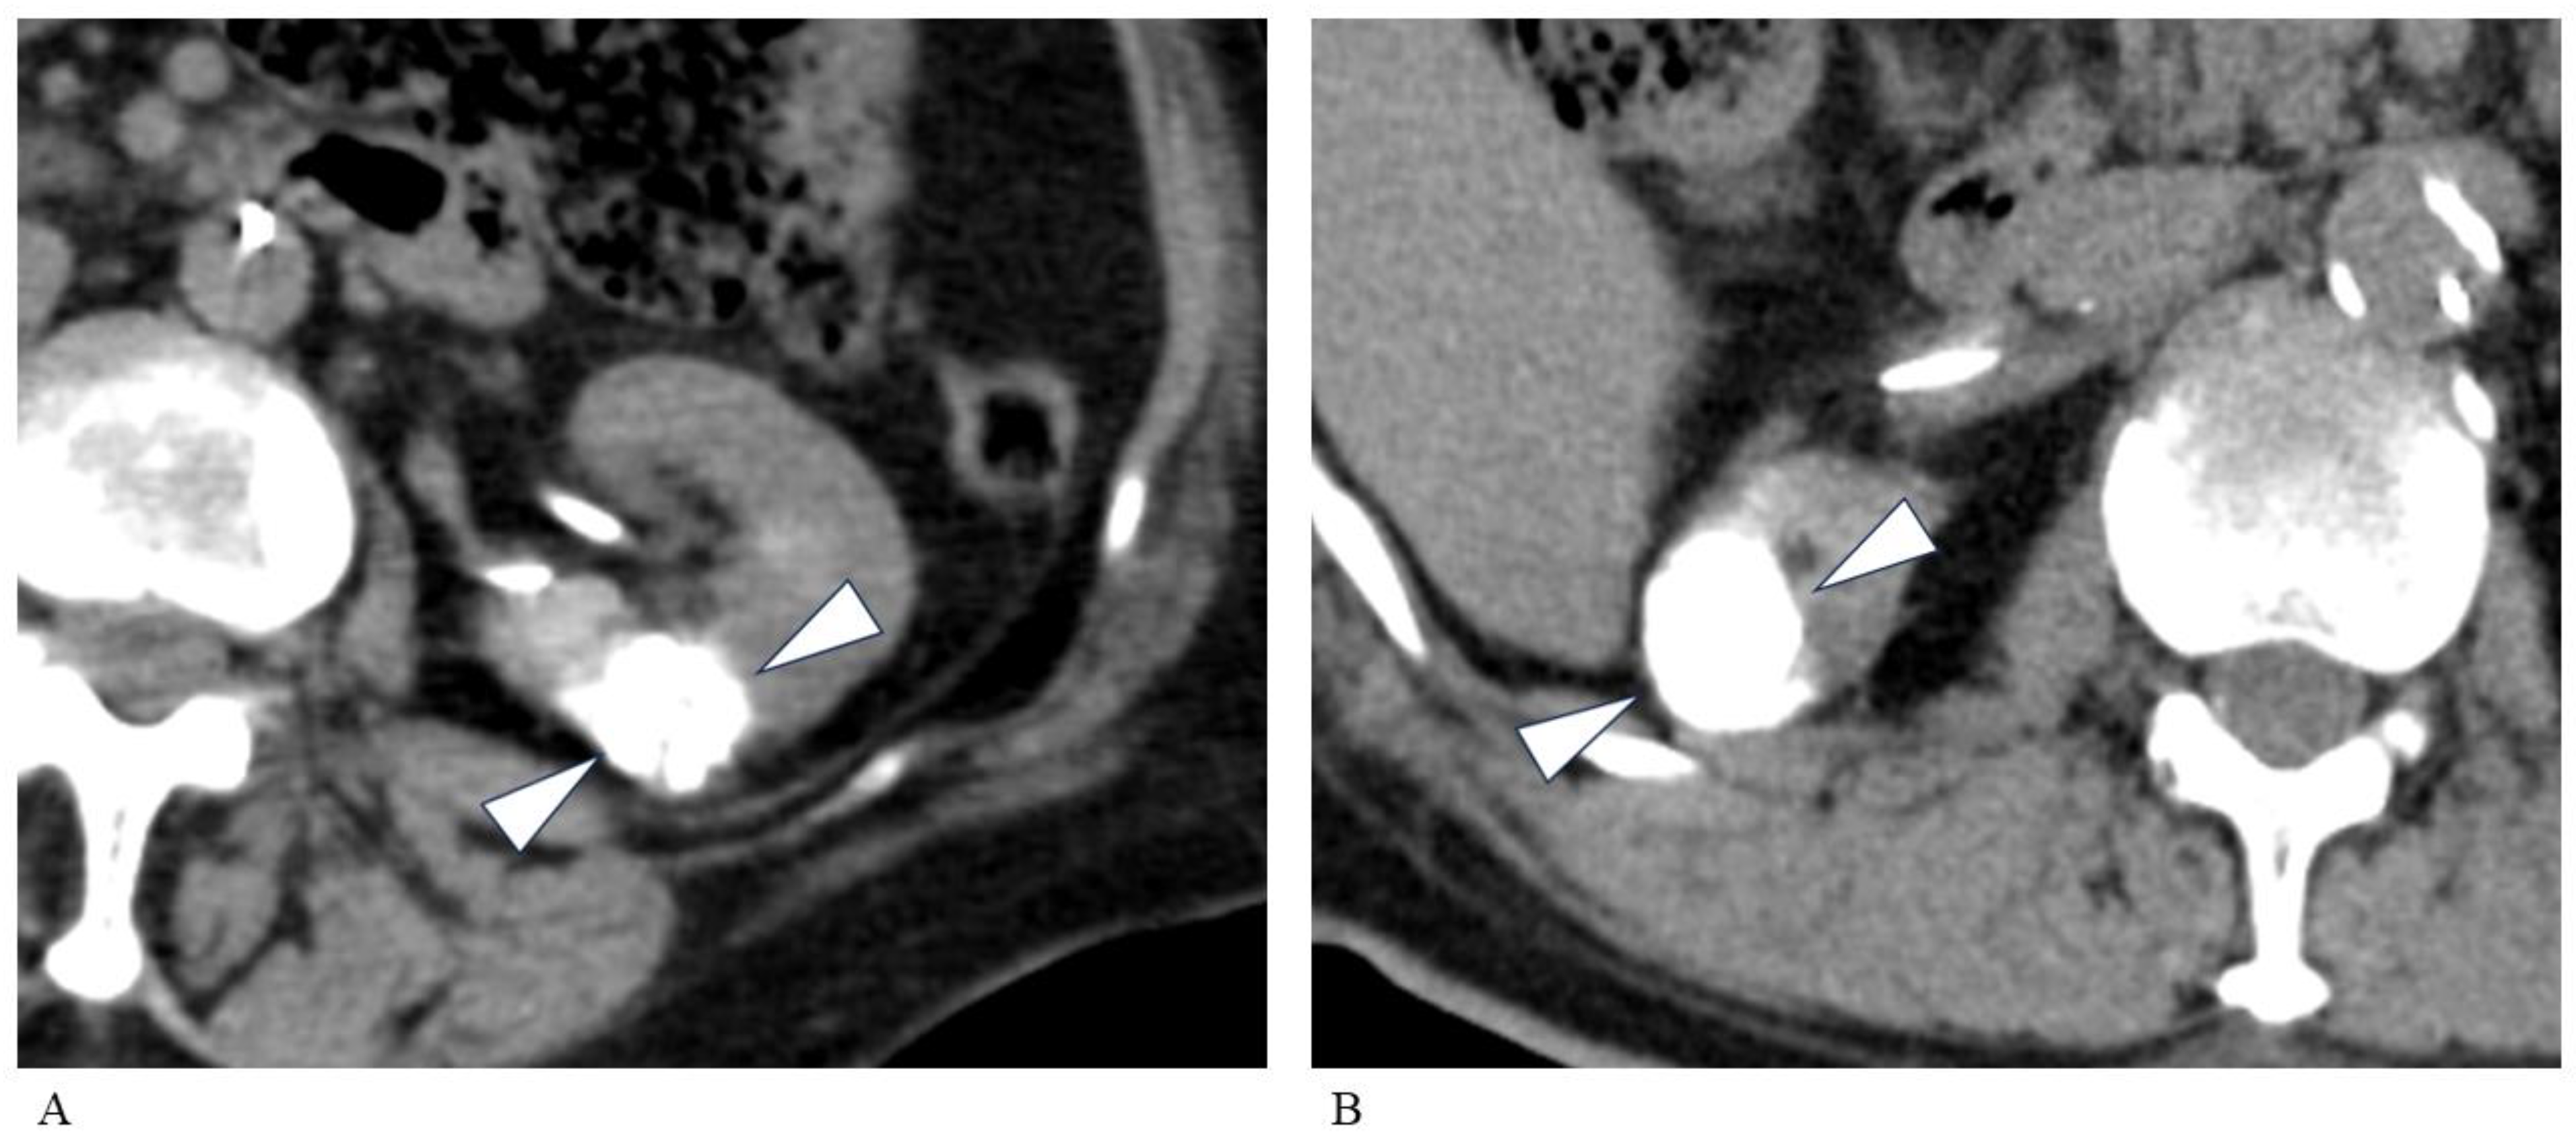

2.2. TAE Technique

2.3. PCA Technique

3.2. Transarterial Embolization

3.3. Percutaneous Cryoablation